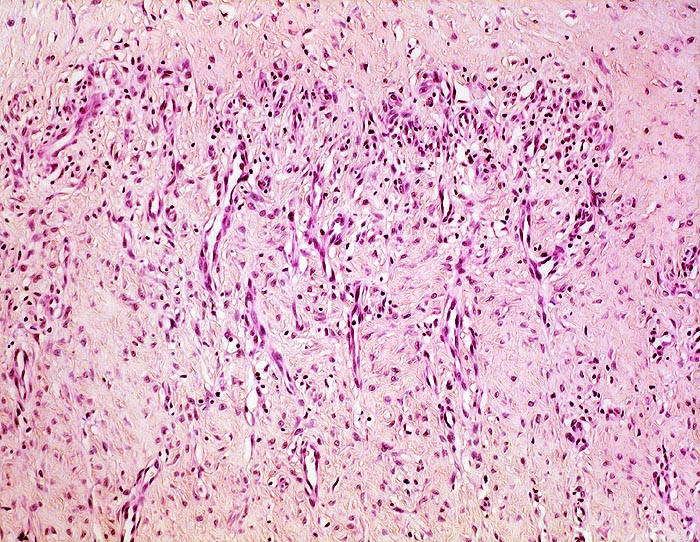

Morphologische Merkmale:

• Eröffnete Bursa mit plumpen Zotten mit kompakten Auflagerungen von hypereosinophilem Fibrin.

• Innenauskleidung durch eine Schicht flacher Synoviozyten.

• Daran angrenzend gefässreiches Granulationsgewebe mit lumennahen Erythrozytenextravasaten und Narbengewebe.

• Weiter aussen folgt Fettgewebe mit breiten Bindegewebssepten.